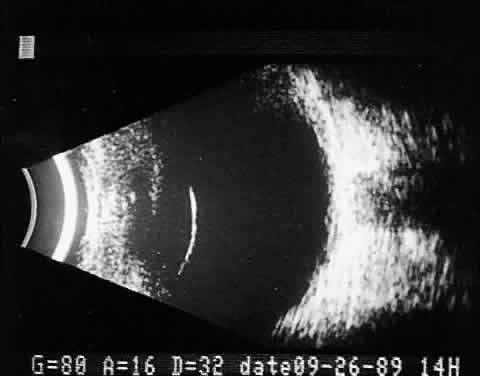

Ocular and orbital foreign body patients require the most careful ultrasonic evaluation, as well as multiple ancillary tests, to provide sufficient diagnostic information. Like ocular trauma, these injuries usually occur unexpectedly and involve high-velocity projectiles. Patient histories are understandably poor or intentionally misleading. Because most foreign bodies are metallic and visible radiographically, appropriate head position for anteroposterior and lateral x-rays of the involved eye and orbit is critical. Routine radiographic imaging quickly supplies information concerning the number, size, and shape of metallic foreign bodies, as well as the presence of any intraocular air. Small bubbles that enter the globe at the time of injury and remain within the vitreous can be confused ultrasonically with small metallic foreign bodies. The large acoustic impedance mismatch between vitreous and air is similar to that between vitreous and metal. Computed tomography scans are extremely helpful in foreign body localization, although it is often difficult to pinpoint the exact intraocular or extraocular position of metallic foreign bodies close to the ocular wall. Metal detection devices add information about the magnetic or nonmagnetic properties of intraocular metallic foreign bodies. Until the magnetic qualities of any potential intraocular foreign bodies are determined, magnetic resonance imaging should not be performed. Ultrasound evaluation in patients with intraocular foreign bodies provides extremely useful additional information concerning associated ocular injuries and another method for localization, especially with nonmetallic intraocular foreign bodies not visible using x-ray techniques. Ultrasonically, foreign bodies have great reflectivity once the examining beam is placed perpendicular to a reflective surface of the foreign body. These abnormalities remain visible even with extreme attenuation of the examining signal (Fig. 16). Many metallic foreign bodies, especially those that are round or spherical, demonstrate “ringing,” a string of reflections that extend posterior to the foreign body in the form of a cometlike tail. Ringing is an ultrasound artifact produced by multiple “ping-pong” reflections of sound pulses within the foreign body before they return to the examining probe. The string of returning echoes produces an unusual display image.